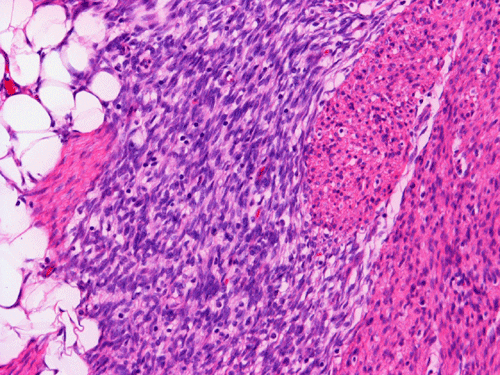

The excised mass is composed of an intermingled arrangement of mature adipose tissue, densely packed primitive spindle cells with small amount of cytoplasm, and mature appearing spindle cells with substantial amount of cytoplasm that gives the appearance of smooth muscle (Panel  A). Abrupt transition between the three elements are common (Panel B). The densely packed, small primitive spindle cells have elongated, cigar-shaped nuclei with amphophilic cytoplasm. Pleomorphism and mitotic figures are not seen. A small number of lymphocytes are present among these cells (Panel C). In areas with appeance of smooth muscle, the cells have elongated, sometime wavy nuclei without significant pleomorphism or mitosis (Panel D). Areas with thick, wavy collagen fibers admixed with benign appearing spindle cells are also present (Panel E and F) and some of these areas are more loosely packed than the other areas which may mimic the appearance of a neurofibroma. In contrast to other areas, these collagenous areas merge imperceptibly with the more cellular areas. In some of the densely packed spindle cell areas, there are small packets of loosely packed cells that give a myxomatous morphology on high magnification (Panel G and H).

Histologically, FHI has a triphasic organoid pattern with three distinct types of tissues: fibrous tissue; primitive mesenchyme appearing tissue; and mature adipose tissue. The fibrous tissue consists of well-differentiated spindle cells of fibroblastic/ myofibroblastic appearance admixed with a variable amount of collagen fibers. The dense fibrous tissue may form a fibrous core or at the center of the lesion. The primitive mesenchyme appearing tissue consists of sheets of undifferentiated spindle cells or stellate cells with an amphophilic and inconspicuous cytoplasm. Often these cells arrange in a concentric pattern and form whorls or characteristic ball-like structures in a vascular, mucoid matrix. Scattered lymphoid cells and extravasated erythrocytes are common findings in these areas.  The relative proportions of these three components vary in different cases greatly.